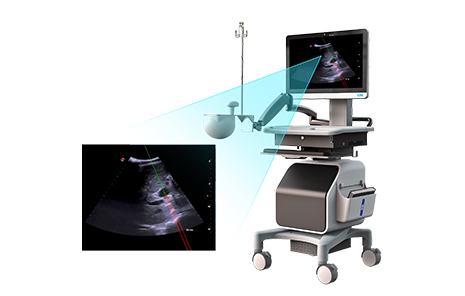

УлБЩґІПЦУРНЕЅбDSAЎўCTµИТЅС§У°ПсµДµзґЕµјєЅЧ°±ёІо±рЈ¬ґЛЧ°±ёН»ЖЖБЛµзґЕ¶ЁО»“їЁІ±ЧУ”КЦТХЈ¬НЁ№эЅ«µзґЕµјєЅУлі¬ЙщУ°ПсНЕЅбЈ¬КµПЦБЛЅйИлКЦКхµДИ«іМКµК±їЙКУ»ЇЎЈёГЧ°±ёµјєЅѕ«¶И≤1.5mmЈ¬ФЪЙжј°ёОЎўµЁЎўЙцЎўЗ°ПЯПЩµИФаЖчµДёЯДС¶ИЙоІїґ©ґМЦРѕЯУРПФЦшУЕКЖЎЈБЩґІКФСй±ЁёжПФКѕЈ¬К№УГёГЧ°±ёµДТ»ґОЅшХлґ©ґМАЦіЙВКґп98.96%ЎЈН¬К±Ј¬ёГЧ°±ёїЙЅµµНёЯДС¶Иґ©ґМКЦКхµДС§П°ДС¶ИЈ¬МбЙэTIPSЈЁѕѕ±ѕІВцёОДЪГЕМеѕІВц·ЦБчКхЈ©µИЛДј¶КЦКхµДЖХј°ВКЎЈ